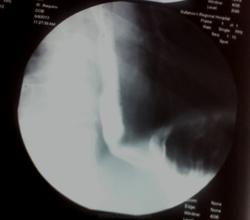

Пациент направлен на скопию желудка с диагнозом ГЭРБ. При исследовании меня смутил данный "перегиб" пищевода под прямым углом. Вариант развития? или что то придавило?

При исследовании меня смутил данный "перегиб" пищевода под прямым углом.

"Перегиб" на одном снимке, или нескольких?

Аппарат "Опера". Режим автоматический. В положении стоя и лежа "перегиб" не меняется.